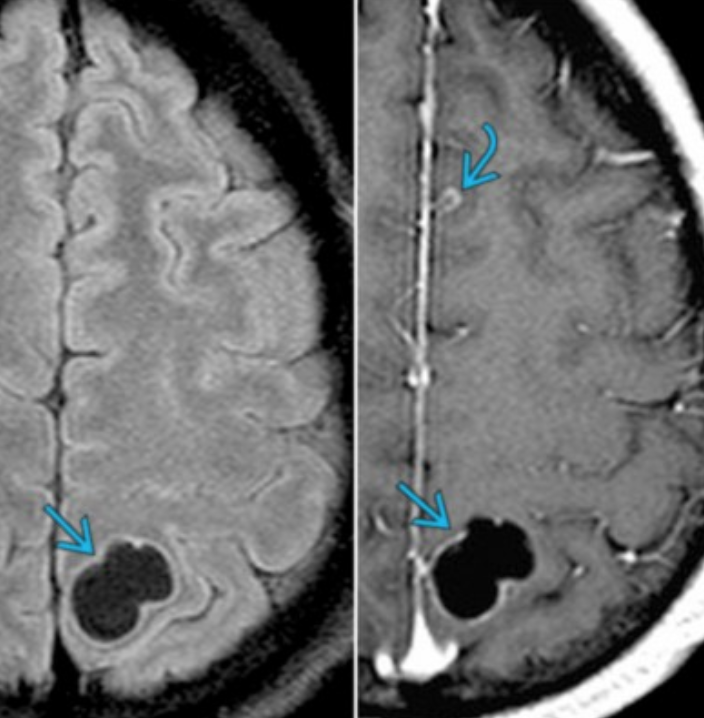

• Cystic lesion with dot in the center

• Other presentation is multiple grape like (racemose) lesions clustered together (top right image)

• Vesicular (top left)

• Indicates visible larva

• Smooth, thin-walled cyst, isodense to CSF, no edema

• Hyperdense dot within cyst = protoscolex

• Colloid Vesicular (Middle)

• Hyperintense cyst with edema

• Ring enhancing fibrous capsule

• Indicates Dying larva